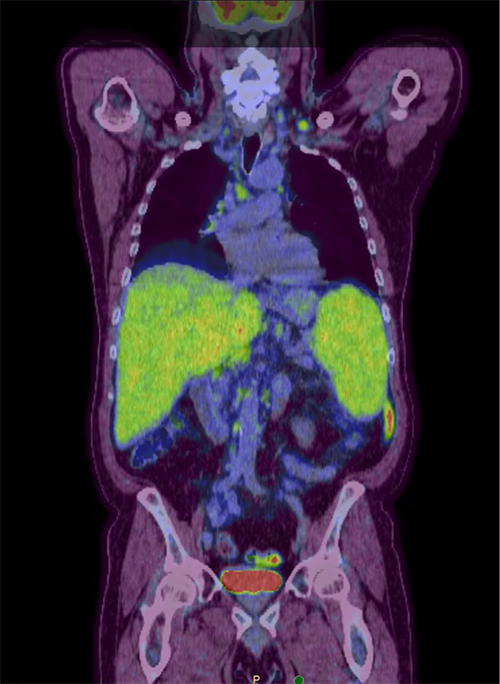

A PET-CT showed Multiple areas of increased activity in supraclavicular lymph nodes bilaterally.